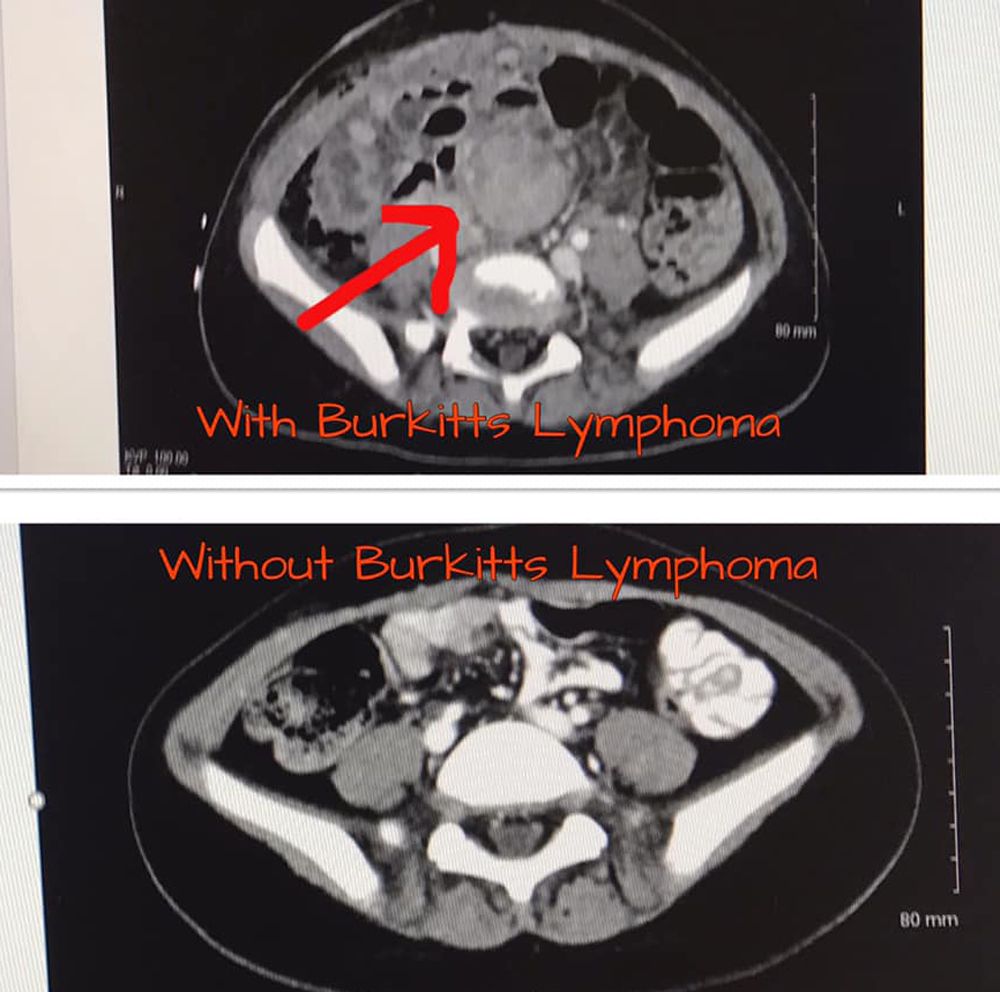

But doctors discovered a mass in the youngster's abdomen, which they had thought was an abscess, was in fact a watermelon-sized tumor, which tests revealed to be Burkitt lymphoma – a rare and fast-growing cancer of the lymphatic system.

The next day, they were referred to the more specialist Addenbrooke's Hospital in Cambridge where, on 2 February, an oncologist officially diagnosed Olivia with Burkitt lymphoma – which, according to Cancer Research, is seen in just 210 new cases each year in the UK and less common in females.

By April, after five rounds of chemotherapy, Olivia had a progress scan which revealed that much of the original tumor had gone.

All that remained was a flat, “fried egg-shaped" mass over her uterus.